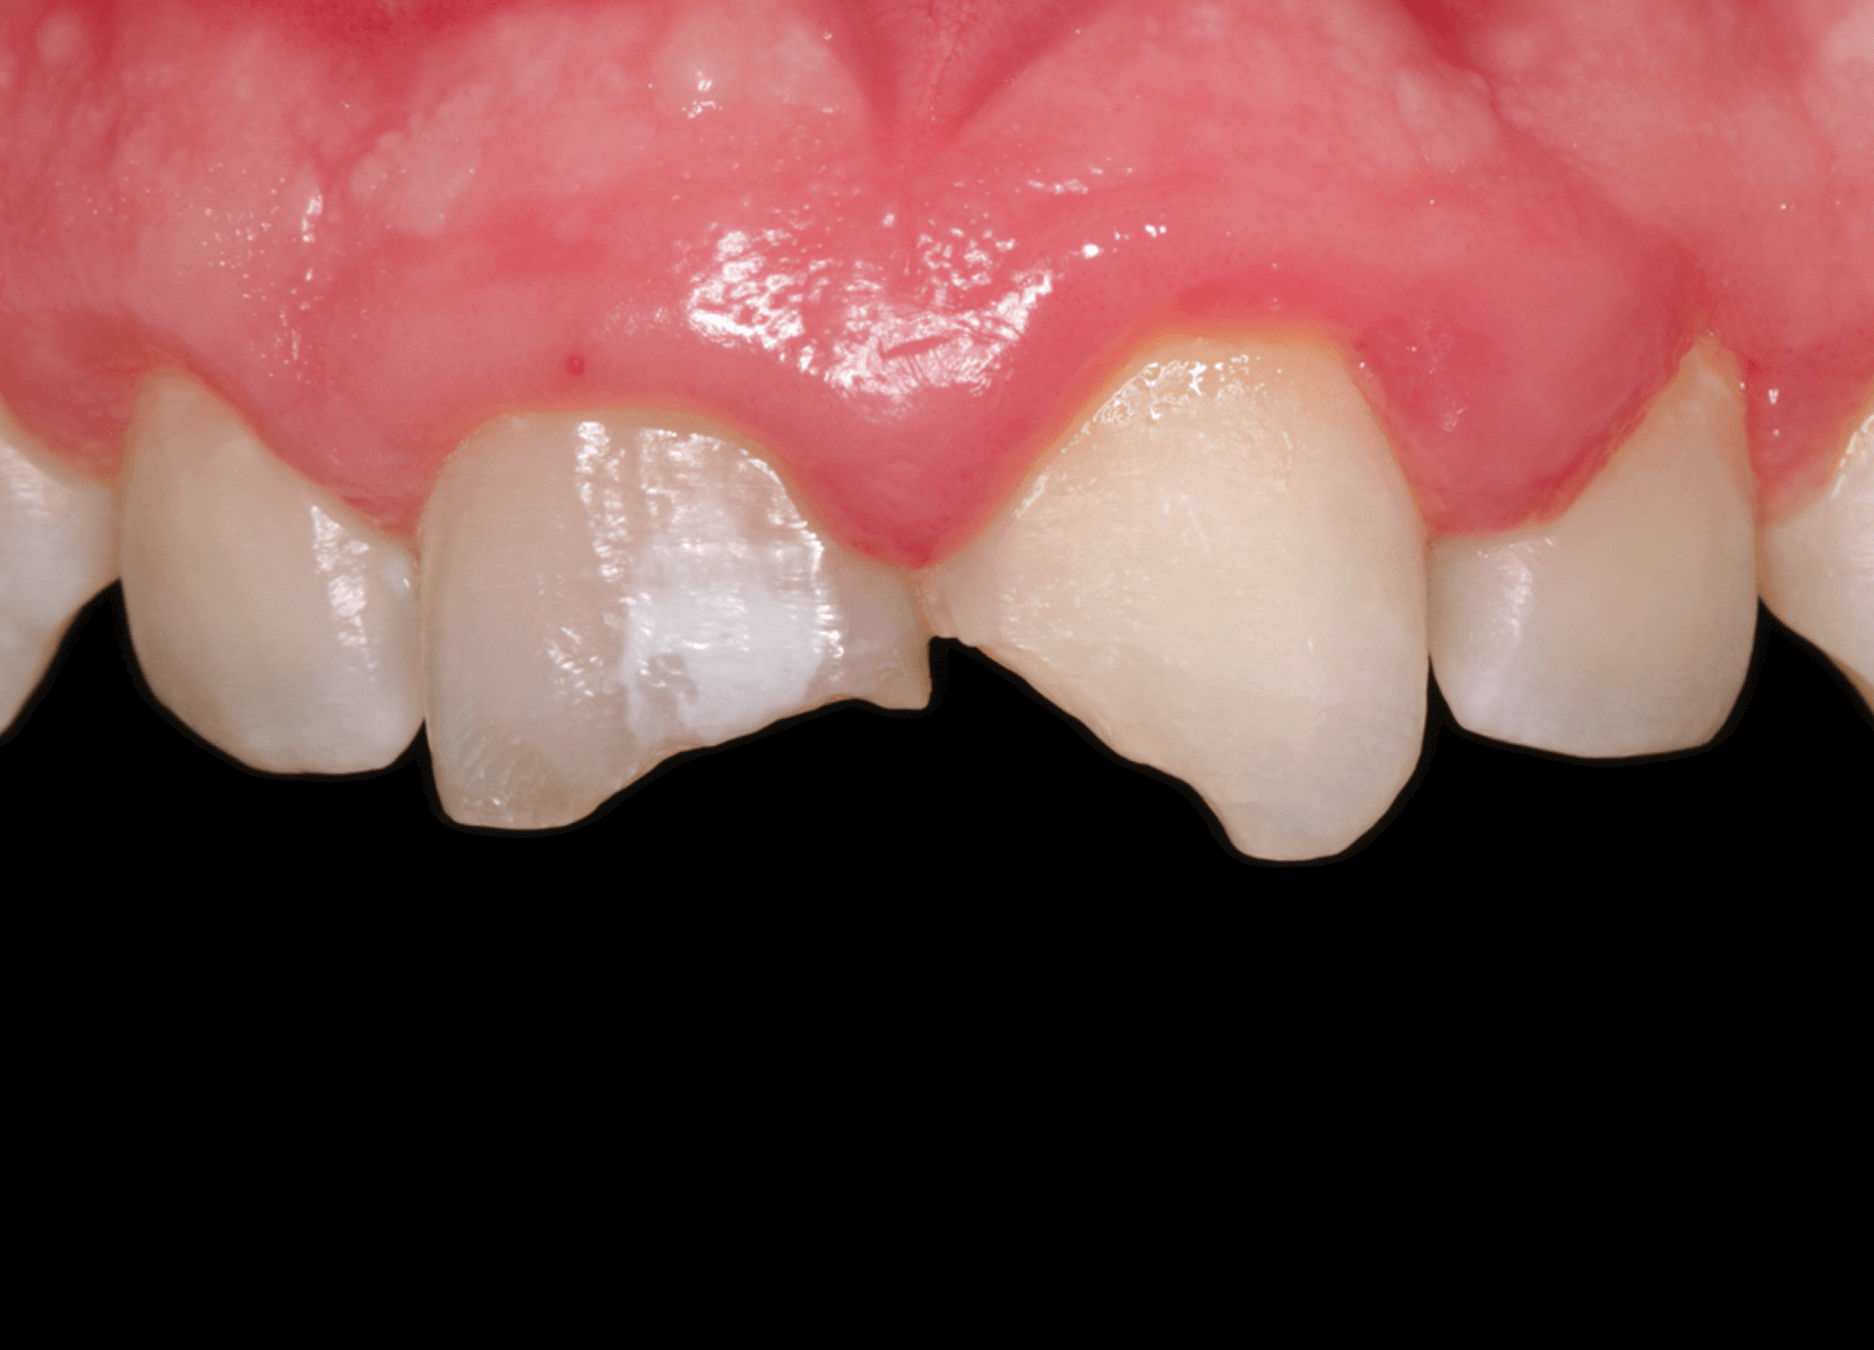

1. Ребенок, перенес травму зубов около 5 лет назад, стоматологическая помощь не была оказана своевременно. (Фото 1)